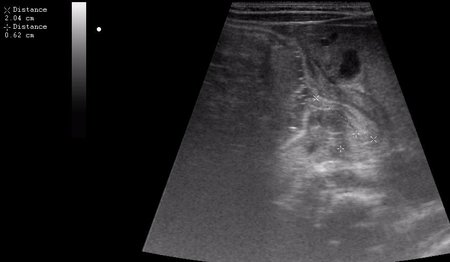

Ребёнок 1 месяц 10 дней от родy, с отсуствием прибавки в весе.

Hypertrophic pyloric stenosis.

Criteria:

1.Pyloric channel > 12 mm in length

2.Muscular layer thickness > 3-4 mm

3.Donuts sign at transverse scanning